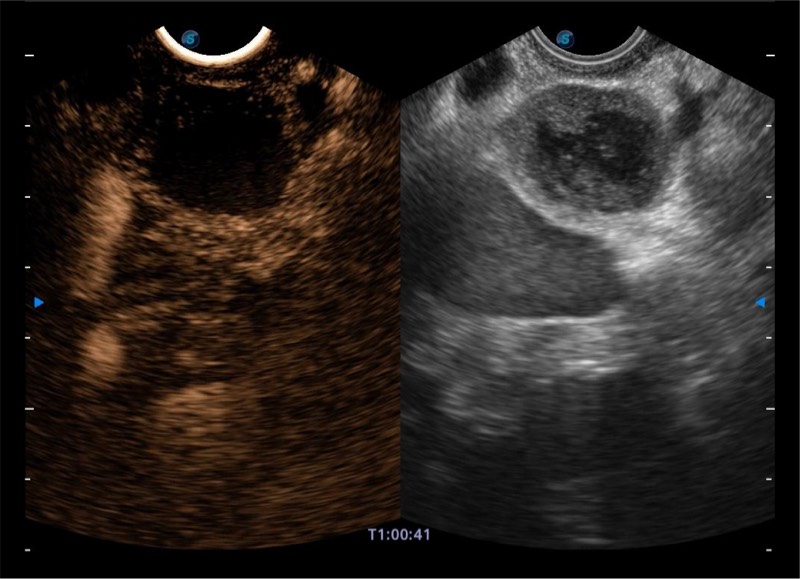

基于二十年的超声技术积累,乐玩lewin国际提供了最新一代的独立超声主机,在提供高质量图像的同时满足多学科使用。具备常见多普勒技术并提供弹性成像、声学造影等高端影像技术。新一代传感器具有更强的抗干扰能力并减少图像伪影。

4-12MHZ宽频输出